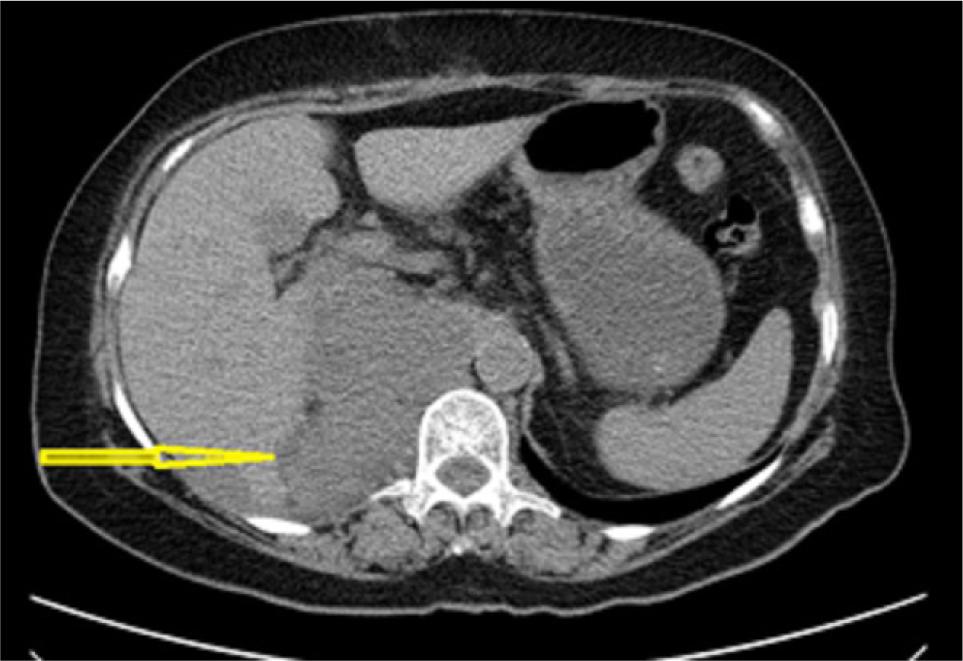

Physical examination revealed only mild right flank tenderness with right palpable, nonmobile mass. Urine analysis showed microscopic hematuria (15/20 RBCs/HPF). The routine blood tests were within the normal range. Ultrasonography (US) showed a 20×25 cm solid hypoechoic mass in the right med and lower pole of the kidney. A chest, abdomen, and pelvic computed tomography (CT) scan was done, which showed a 20×25×8 cm heterogeneous solid mass in the middle pole that extended to the lower pole of the right kidney with delayed enhancement . There was no evident local invasion or metastases in the chest CT scan. However, the tumor was pressing the liver, and no defined fat planes were seen (Figure 1).

Figure 1: CT scan of the abdomen demonstrates the right renal mass.

Figure 4: Postoperative abdominopelvic CT scan demonstrates local recurrence and liver metastasis (Arrow).